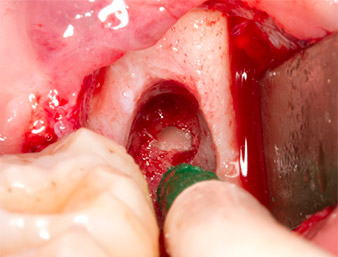

Periapical inflamed tissue was also removed very carefully with a manual excavator. Fig. 12 shows the empty alveole with exposed inferior alveolar nerve.